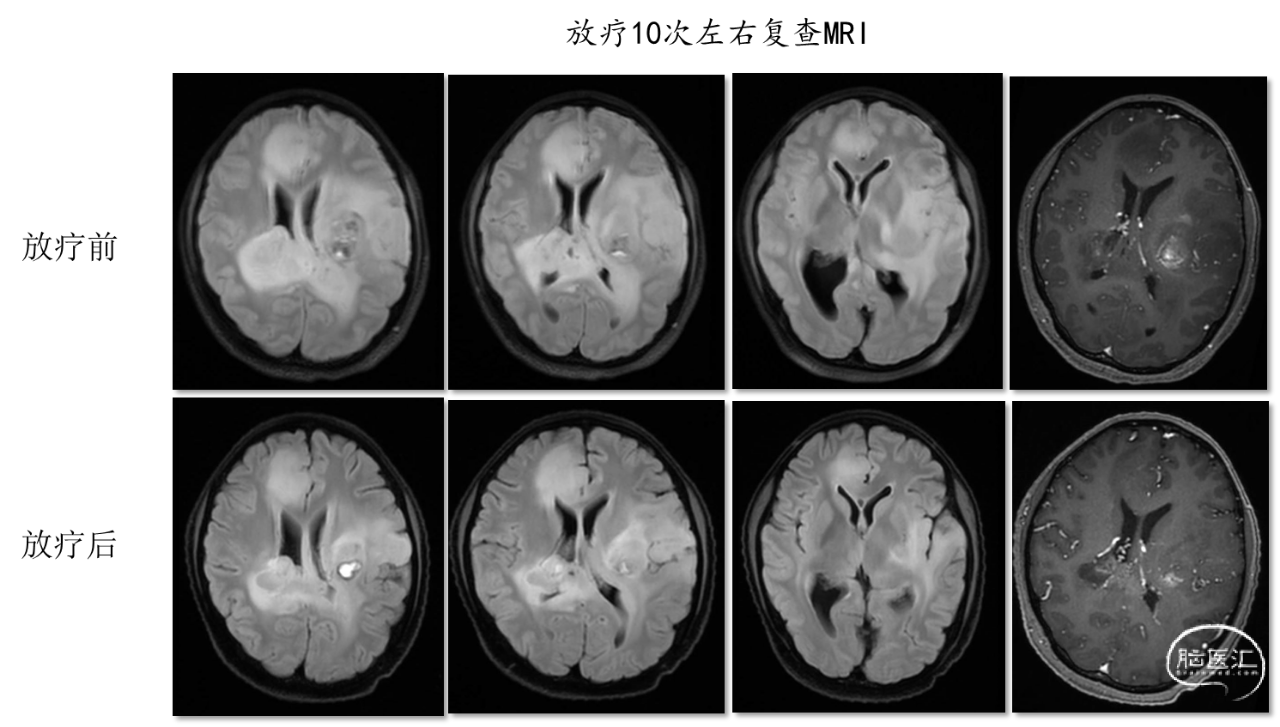

患者活检术后一周左右出现意识模糊,右侧肌力I级,较前显著下降。复查头部CT未见穿刺部位新发出血,复查头部MRI病灶较前增大。考虑病情进展,于2020年12月22日至2021年2月3日在我院肿瘤放化疗科开始行贝伐单抗联合替莫唑胺同步电场放化疗(PTV-GTV1=60Gy/30F, PTV-GTV2=54Gy/30F)。放疗10次后患者意识由嗜睡转为清楚,患侧肌力III级,复查头部MRI示病灶较前缩小。放疗20次左右患者一般情况较前进一步好转,患侧肌力V-级,复查头部MRI显示T2及增强病灶较前明显缩小。